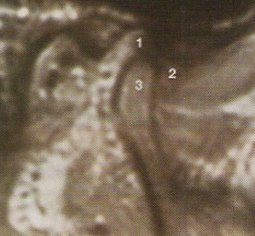

De ésto nos van a informar en radiología al realizar una RMN de ATMs. Esta prueba se muestra especialmente útil y superior a los restantes métodos de diagnóstico por imagen, en el estudio de la posición del disco articular y de sus anomalías de posición (desplazamientos discales) y estructurales. En condiciones normales, cuando se explora la ATM en boca cerrada y en cortes sagitales, el disco aparece como una cinta grisácea oscura situado entre el cóndilo y la eminencia temporal; el extremo anterior (banda anterior) se halla en la posición horaria de las 9 mirando a la cima de la eminencia, y el extremo posterior (banda posterior), más grueso, en la posición de las 12 de la cabeza condílea.

La banda posterior en relación con la cabeza condílea es el punto de referencia para apreciar la posición y desplazamiento del disco; así, se considera que hay desplazamiento discal anterior cuando, con la boca cerrada, el disco está por delante de la posición horaria de las 12 con respecto a la cabeza condílea.

El fundamento de esta prueba está en la teoría cuántica. Se detectan pequeñas señales emitidas por el núcleo de los átomos de hidrógeno, que se encuentran presentes en el agua y en las grasas del cuerpo humano, cuando son expuestos a un campo magnético. Las imágenes de RMN muestran distintos contrastes de grises dependiendo de la energía de radiofrecuencia y de la riqueza en átomos de hidrógeno del tejido explorado; así, el tejido adiposo y el hueso esponjoso medular son de alta densidad y aparecen de color más o menos blanco, la cortical ósea es de baja densidad apareciendo en color negro, y el músculo que es de intensidad intermedia aparece en tonos grisáceos. El disco articular es de baja intensidad y tiende a aparecer en gris-negro.